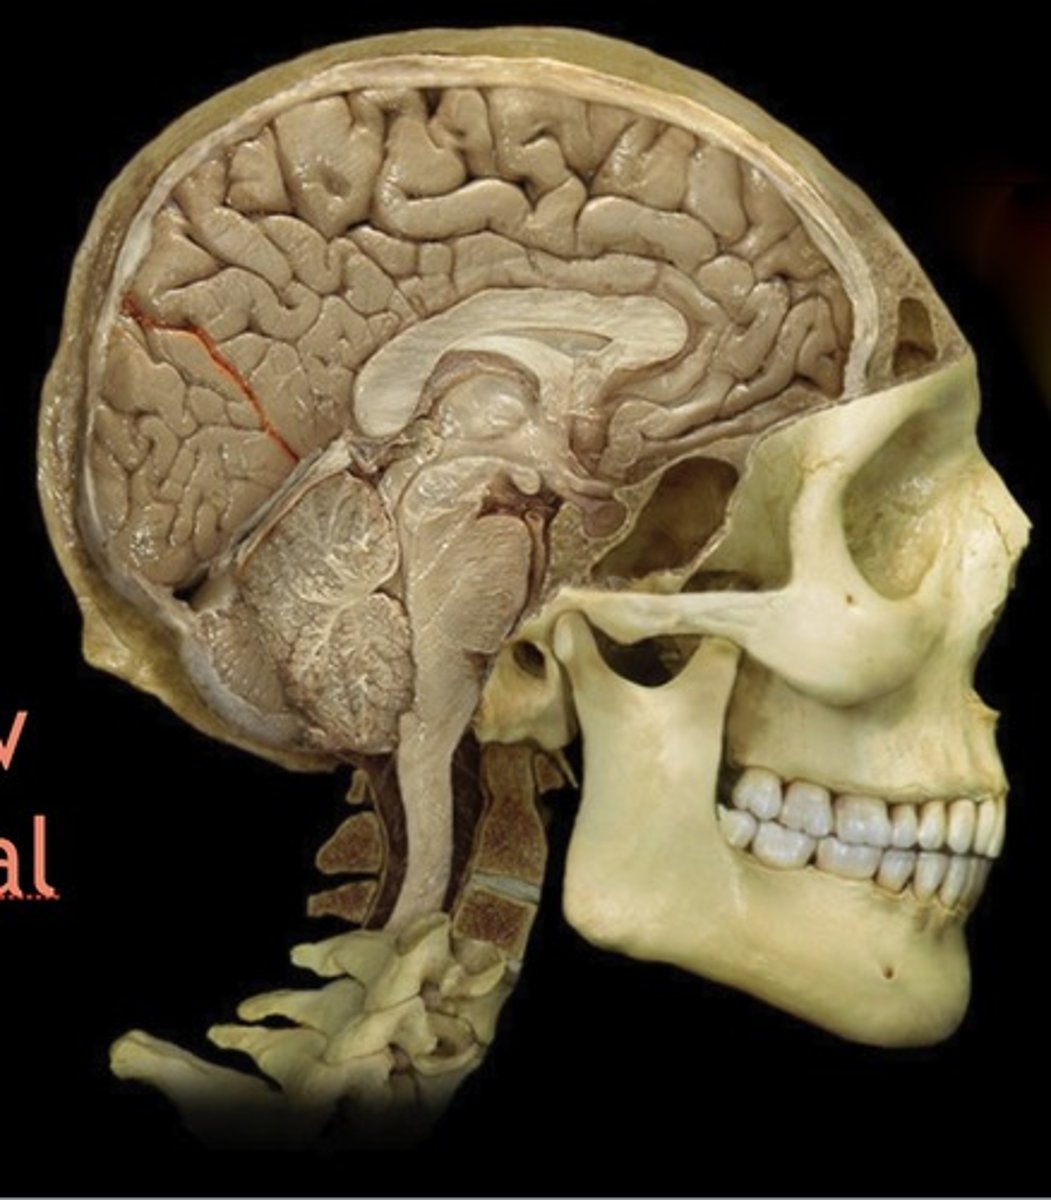

Corpus Callosum

Name this structure

Parieto-occipital sulcus

Name this structure

Thalamus

Name this structure

Hypothalamus

Name this structure

Pineal gland

Name this structure

Mamillary Body

Name this structure

Pituitary gland

Name this structure

brainstem

Name this structure

Midbrain

Name this structure

Pons

Name this structure

Medulla Oblongata

Name this structure

Cervical Spinal Cord

Name this structure

Third Ventricle

Name this structure

Fourth Ventricle

Name this structure

Central Sulcus

Name this structure